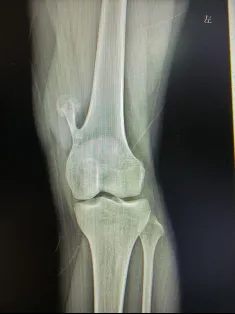

(影像说明:左膝关节正位X线片,左侧股骨远端可见典型带蒂骨性突起,背离关节面生长,骨皮质、骨髓腔与宿主骨相延续,这是骨软骨瘤特有的影像学表现)

从片子上可以清晰看到:女孩左侧大腿下端靠近膝盖处,骨头向外长出了一处明显的骨性凸起。

膝关节每次屈伸活动时,这块多余的骨质会反复摩擦周围的肌肉、肌腱和滑囊,持续产生机械刺激,久而久之形成顽固性酸痛,尤其活动后加重,严重影响日常行走与生活。